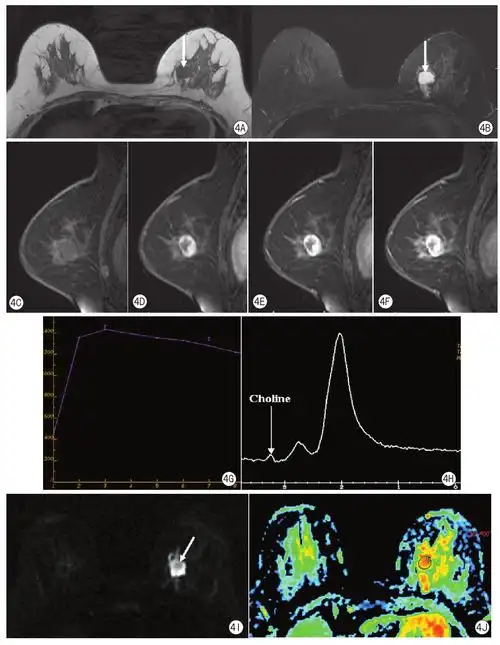

磁共振成像对形态学表现为良性特征的乳腺恶性肿瘤诊断价值